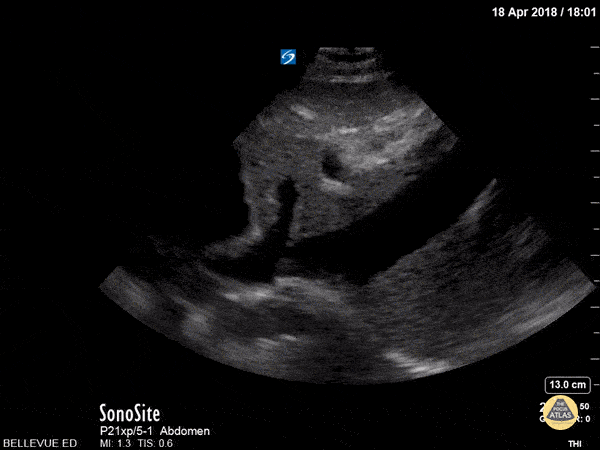

In this longitudinal subxiphoid view, we see the liver in the center and beating heart to the left of the screen. The IVC in long axis empties into the right atrium. A hepatic vein is seen draining into the IVC just prior to its confluence with the heart. Hannah Kopinksi and Dr. Lindsay Davis - NYU Emergency Medicine